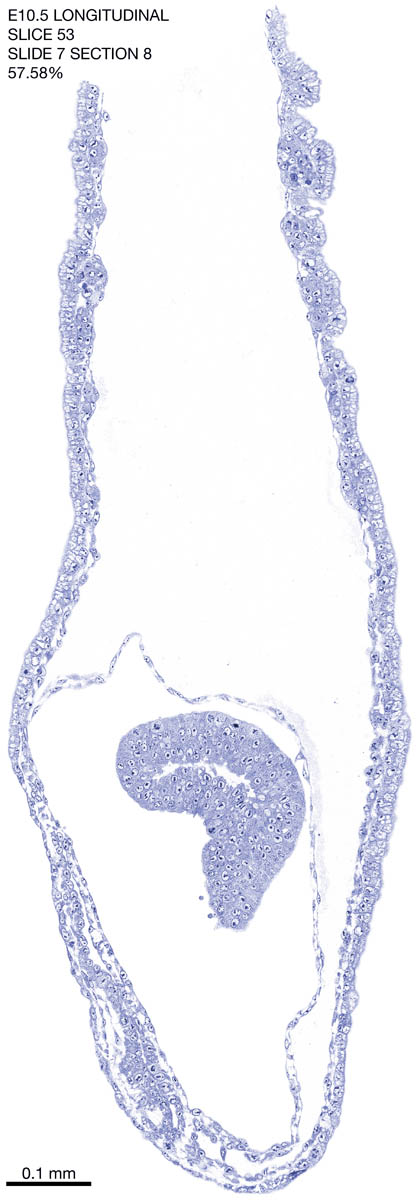

E10.5 Longitudianal Archive This page contains jpg files of ALL SLICES (each 3µm thick) that were scanned of the E10.5 longitudinally cut specimen. Download: Large | High Res Download: Large | High Res Download: Large | High Res Download: Large | High Res Download: Large | High Res Download: Large | High Res Download: Large | High Res Download: Large | High Res Download: Large | High Res Download: Large | High Res Download: Large | High Res Download: Large | High Res Download: Large | High Res Download: Large | High Res Download: Large | High Res Download: Large | High Res Download: Large | High Res Download: Large | High Res Download: Large | High Res Download: Large | High Res Download: Large | High Res Download: Large | High Res Download: Large | High Res Download: Large | High Res Download: Large | High Res Download: Large | High Res Download: Large | High Res Download: Large | High Res Download: Large | High Res Download: Large | High Res Download: Large | High Res Download: Large | High Res Download: Large | High Res Download: Large | High Res Download: Large | High Res Download: Large | High Res Download: Large | High Res Download: Large | High Res Download: Large | High Res Download: Large | High Res Download: Large | High Res Download: Large | High Res Download: Large | High Res Download: Large | High Res Download: Large | High Res Download: Large | High Res Download: Large | High Res Download: Large | High Res Download: Large | High Res Download: Large | High Res Download: Large | High Res Download: Large | High Res Download: Large | High Res Download: Large | High Res Download: Large | High Res Download: Large | High Res Download: Large | High Res Download: Large | High Res